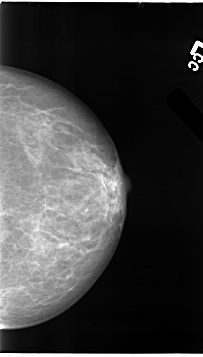

ics_version 1.0 filename B-3101-1 DATE_OF_STUDY 7 11 1996 PATIENT_AGE 48 FILM FILM_TYPE REGULAR DENSITY 3 DATE_DIGITIZED 6 2 1998 DIGITIZER LUMISYS LASER SEQUENCE LEFT_CC LINES 4632 PIXELS_PER_LINE 2632 BITS_PER_PIXEL 12 RESOLUTION 50 NON_OVERLAY LEFT_MLO LINES 4744 PIXELS_PER_LINE 2792 BITS_PER_PIXEL 12 RESOLUTION 50 NON_OVERLAY RIGHT_CC LINES 4720 PIXELS_PER_LINE 2472 BITS_PER_PIXEL 12 RESOLUTION 50 OVERLAY RIGHT_MLO LINES 4696 PIXELS_PER_LINE 2640 BITS_PER_PIXEL 12 RESOLUTION 50 OVERLAY |